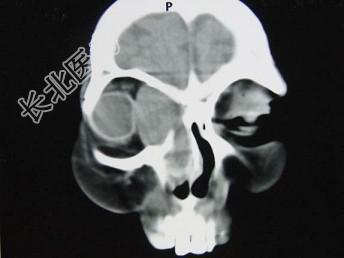

- 单项选择题女,40岁, 右眼反复溢泪伴眼球渐进性突出2年余,眼球运动受限, CT检查如图所示,最可能的诊断是 ( )